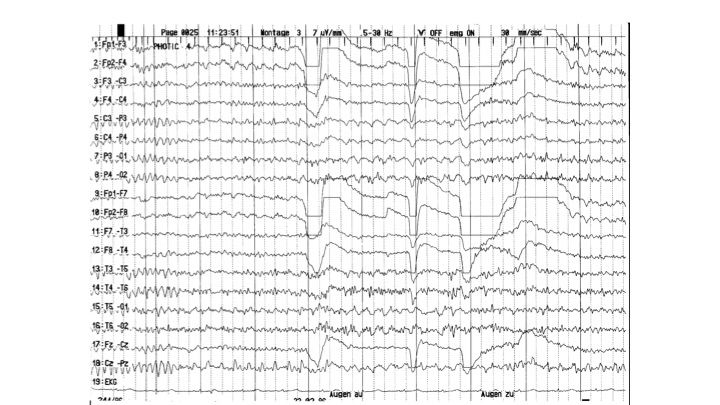

Provokationsmethoden | 37.49 zurück | weiter